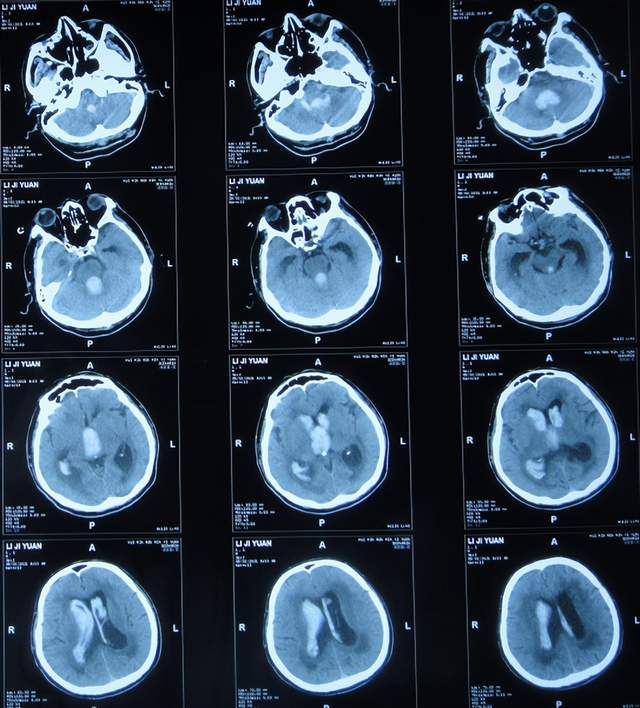

患者于2021年9月2日突发昏迷,急送至当地的山东省滨州市惠民县某医院,查头颅CT示脑出血破入脑室(图-1),急诊行双侧脑室外引流术;脑出血后血压偏低,给予输注入人血白蛋白。

图-1:2021年9月2日头颅CT

术后次日即2021年9月3日,患者意识转清醒,能简单言语,肢体可以遵嘱抬起;查头颅CT示双侧脑室引流术后,脑室积血(图-2)。

图-2:2021年9月3日头颅CT

双侧脑室外引流术后3天即2021年9月5日,查头颅CT示脑室内积血减少(图-3)。

图-3:2021年9月5日头颅CT

双侧脑室外引流术后6天即2021年9月8日,再次查头颅CT示仍有少量积血(图-4);给予常规拔除了双侧脑室外引流管,同时进行了腰大池引流术。

图-4:2021年9月8日头颅CT